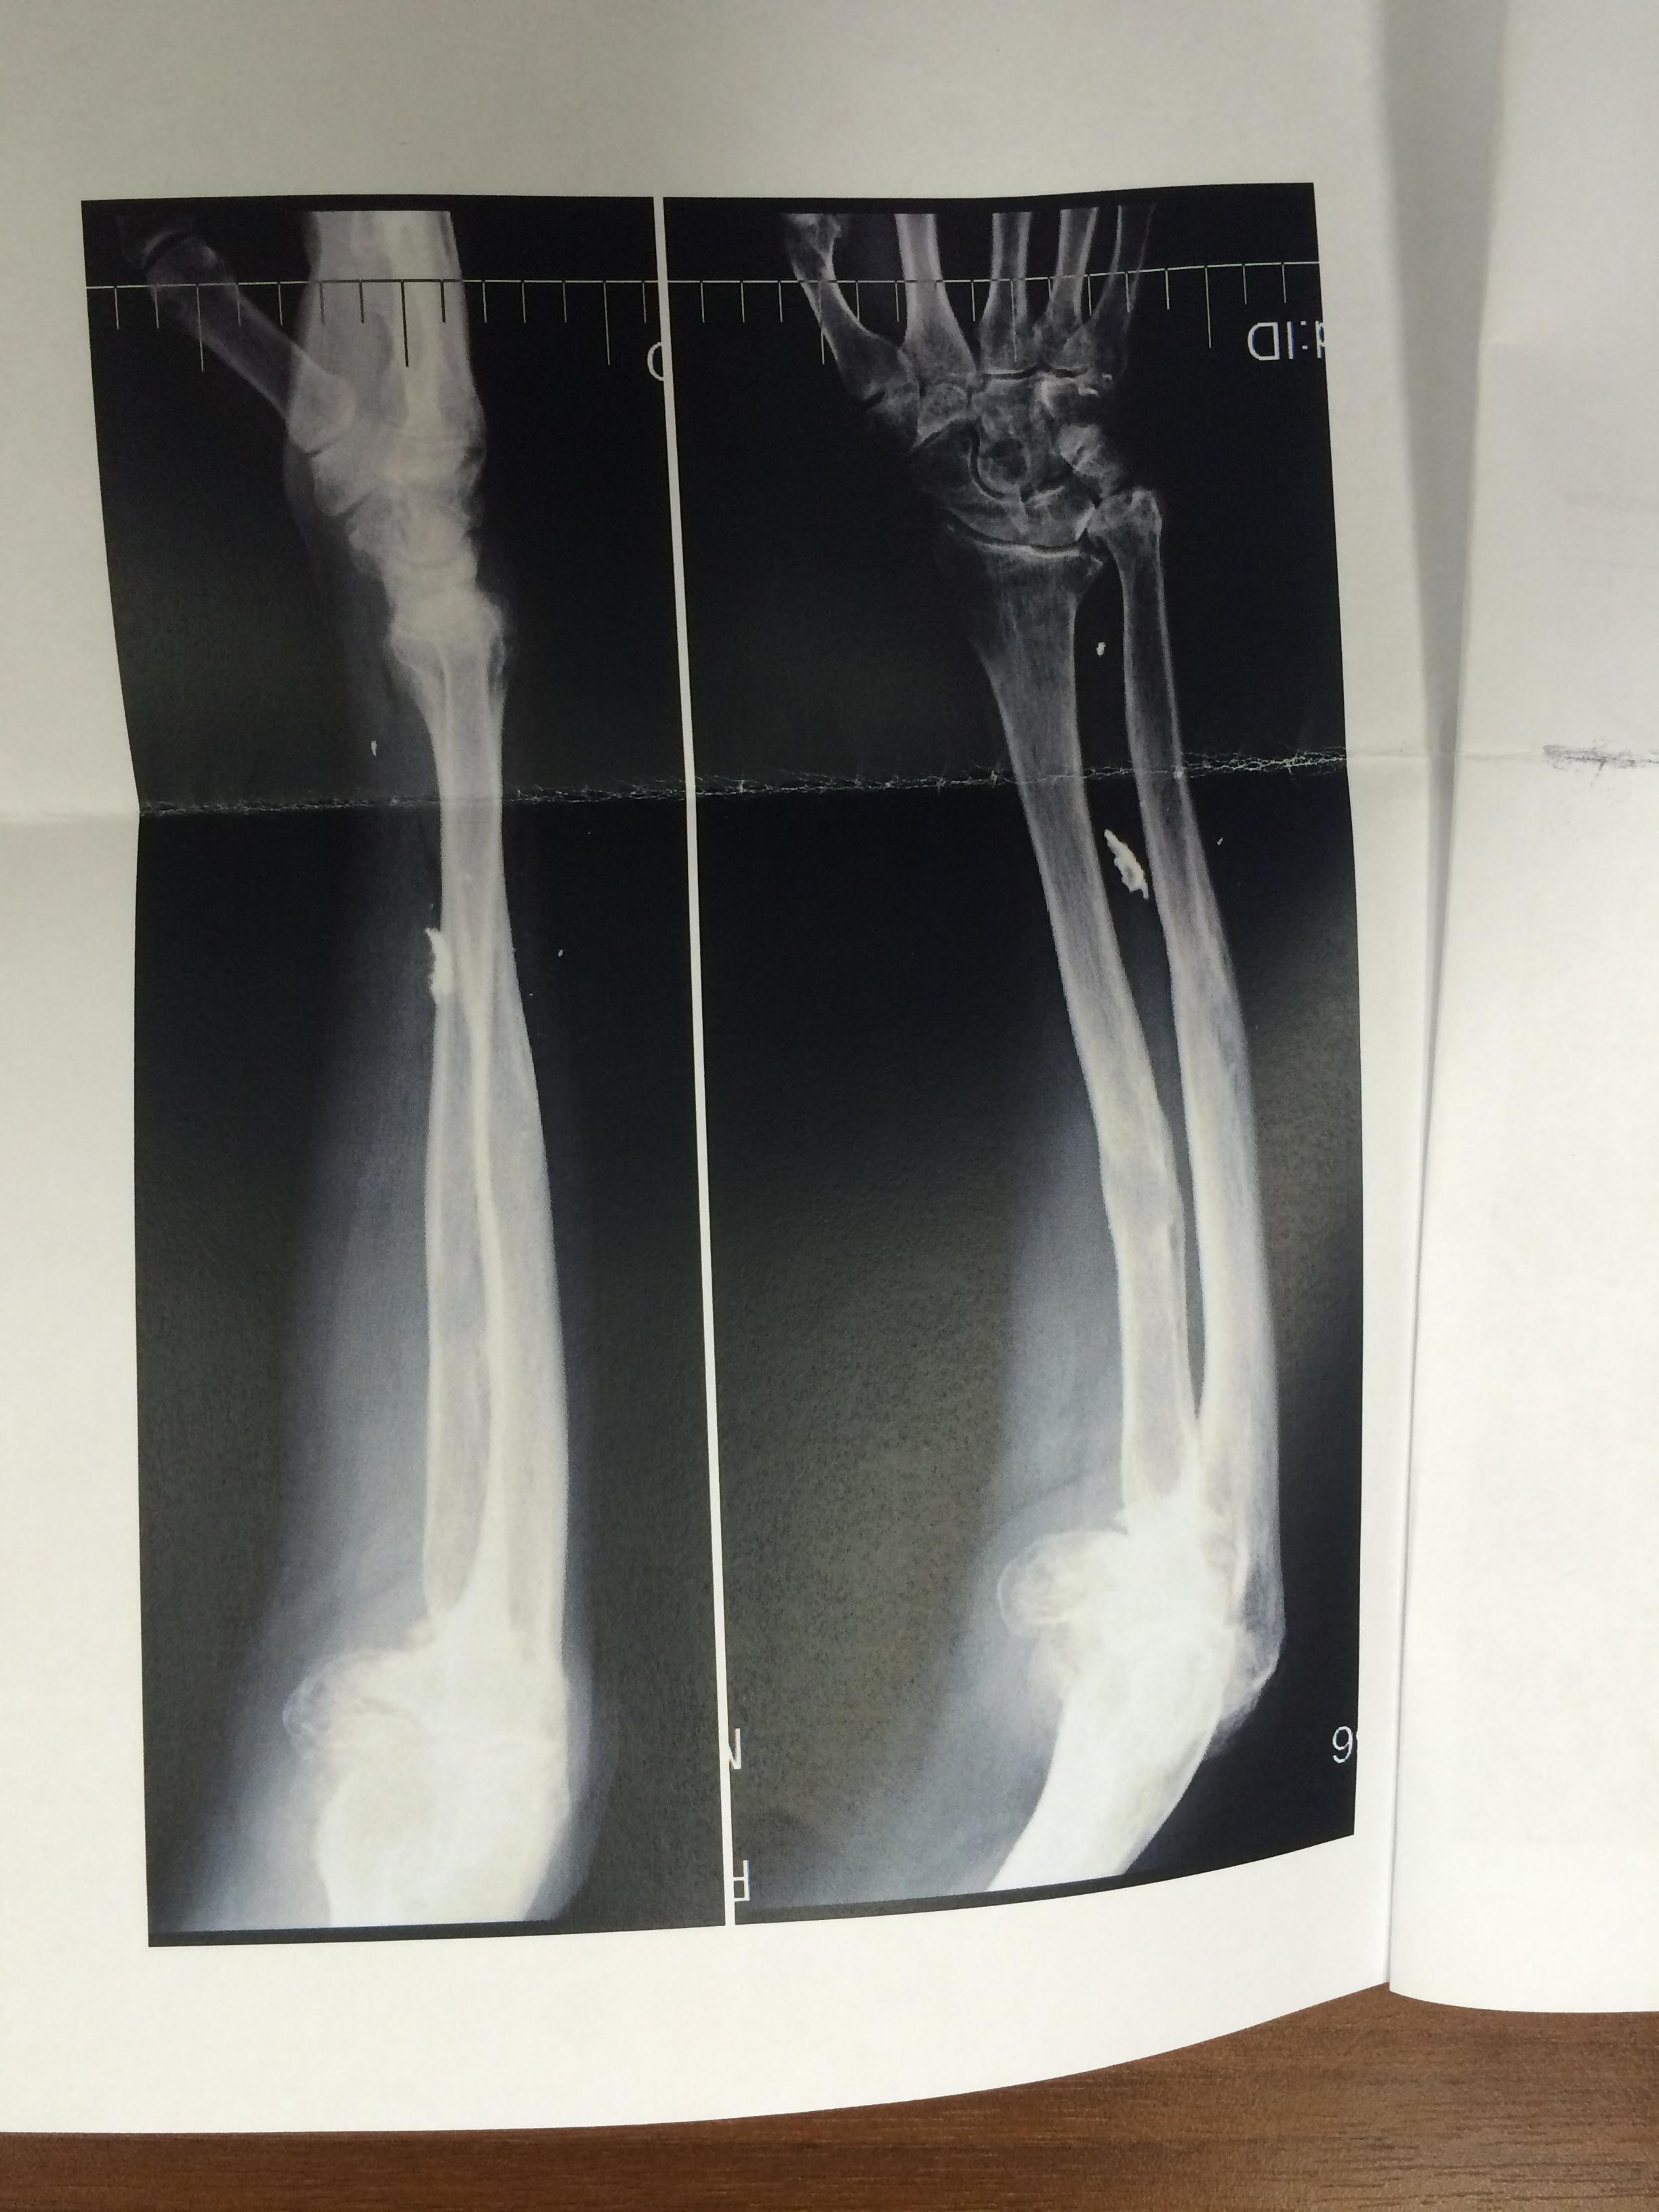

Иллюстрации